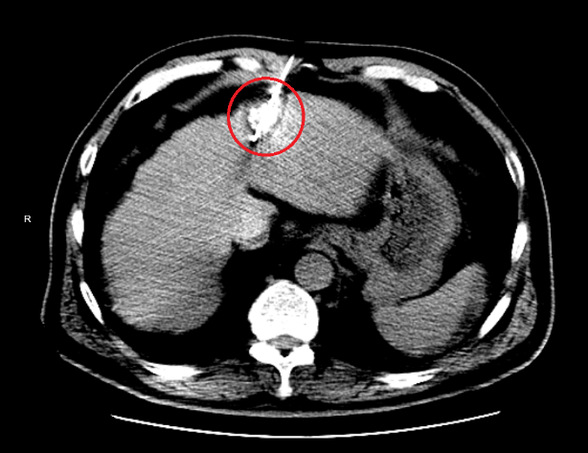

手术在CT室进行,莫庆国主任将一根冷冻消融针通过CT引导逐步进入病灶后,开展CT引导下经皮下氩氦刀肝癌冷冻消融术。

穿刺